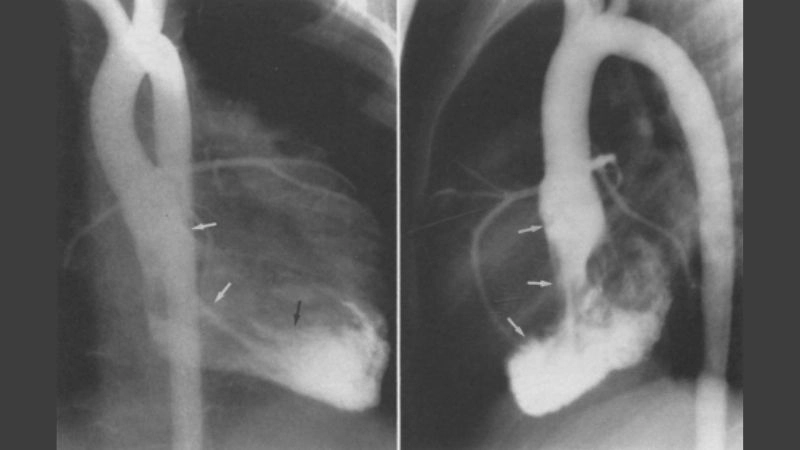

Cardiac fibroma is a rare, benign tumor of the heart composed mainly of fibrous tissue. It often develops in children and may cause symptoms related to heart rhythm and pumping function.